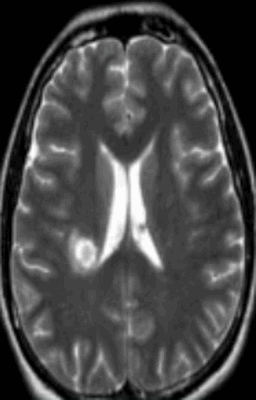

Красным выделен участок ишемии мозга в динамике на МРТ

Ишемический инсульт (МР-сканирование)

Очаги ишемии головного мозга на МРТ

Нарушение кровотока в артериальном бассейне или незамкнутом Виллизиевом круге может сопровождаться формированием обширного участка ишемии. Зона повреждения на МРТ головы будет неправильной формы с нечеткими границами из-за отека. Поражение артерий мелкого калибра выглядит как лакунарный инфаркт (округлая локализованная область изменений).